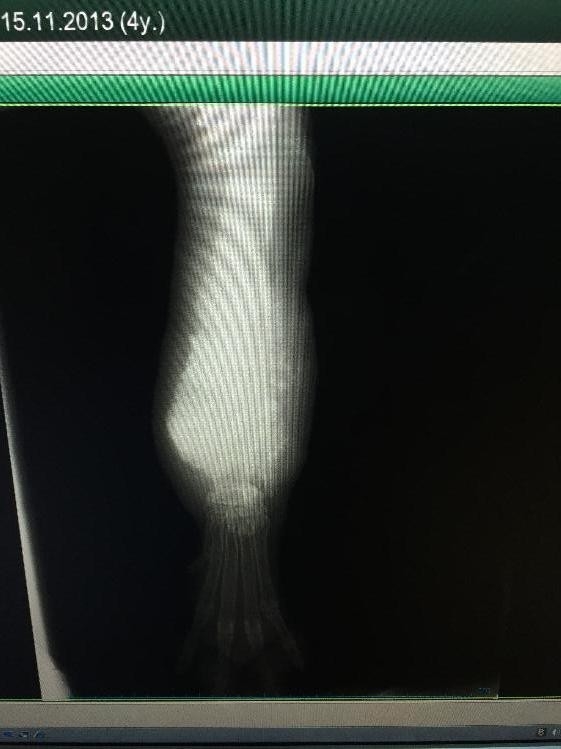

Deniz Öksüzler'in sahibi olduğu 3 yaşındaki kangal köpek, 5 aydan bu yana ayağında şişlik olduğu için yürüyemiyordu. Deniz Öksüzler, antibiyotik tedavisi alan hastasının iyileşmemesi üzerine, ERÜ Veteriner Fakültesi Eğitim Araştırma ve Uygulama Hastanesine başvurdu. İncelemelerde köpeğin bacağında bir tümör tespit edildi. 2 saat süren ameliyat sonucunda, köpek sağlığına kavuştu. Deniz Öksüzler, "Büyükbaş hayvan çiftliğimiz var, oradaki veterinerlerin verdiği antibiyotik tedavisi ile yara bir miktar küçüldü ama daha sonra daha çok büyüdü. Öyle olunca Veteriner Fakültesine geldim. Bacakta bir tümöre rastlandı. Benim isteğim üzerine o bacağı ameliyatla ampute edildi. Şu anda köpeğim sağlığına kavuştu" dedi.

Operasyonu gerçekleştiren Veteriner Fakültesi Cerrahi Anabilim Dalı Öğretim Üyesi Prof. Dr. Gültekin Atalan ise "Bu tür operasyonlar komplike operasyonlardır. Köpeğin iri olması nedeniyle bacağın üst ve alt bölgesinden geçen damarlar oldukça yoğun bir durumdadır. Ve bu damarların inaktif edilmesi gerektiğinden çok dikkatli ve titiz olunması gereken bir operasyondur. Bu tür operasyonları köpeklerle hasta sahipleri arasındaki bir ilişkiden, yakın bağdan dolayı hasta sahiplerinin isteği üzerine yapıyoruz. Köpeklerin eski performanslarını kazanmasını beklemiyoruz fakat yine de tolere edebilir ve uzun süre yaşayabilirler" diye konuştu.